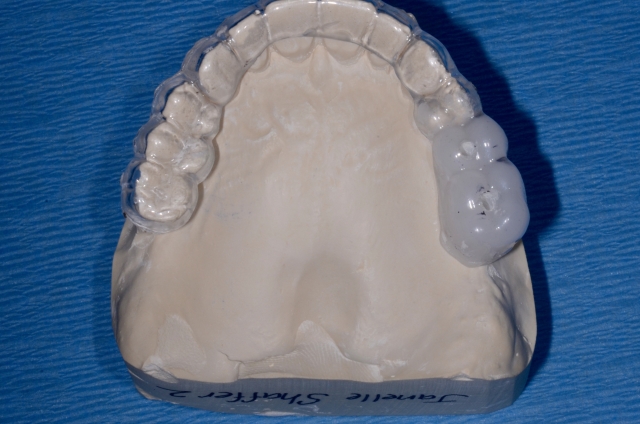

3. Using 1.5 mm clear splint material, do a vacuform over the denture teeth or model of the wax-up.

4. The appliance should then be trimmed so that the desired gingival levels of the final restorations are intact. The remaining teeth should be trimmed back so that 1-2 mm of overlapping acrylic remains to stabilize the template. This is an important landmark for the surgeon.

5. Using a radiopaque self-curing methylmethacrylate mixed to a putty consistency, fill the space left by the denture teeth or wax-up.

6. Trim the excess acylic back to the gingival margins.